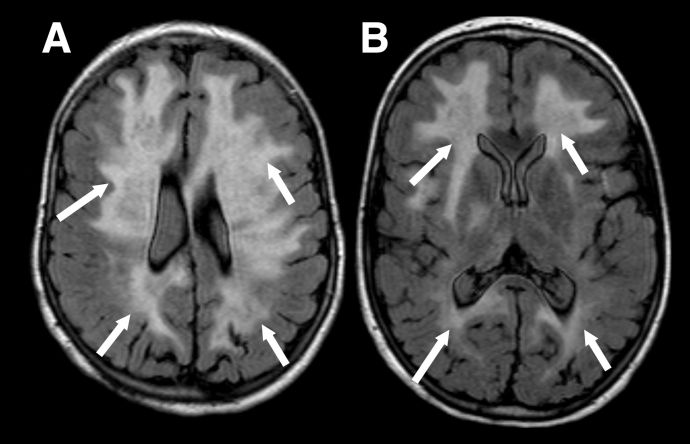

MRI findings depend on presenting phenotype e.g. ADEM vs ON, although there is some crossover. Due to the aforementioned predilection for MOGAD to present as ADEM in younger children the MRI features are inherently different to those seen in adults. MRI features of ADEM are typically bilateral deep white and grey matter lesions which are T2 hyperintense large (>2cm) in size and poorly demarcated (Figure 1). However, MRI findings in pediatric ADEM can demonstrate a “leukodystrophy-like” pattern which includes predominantly confluent and bilateral white matter changes and is associated with a poorer outcome (Figure 2).[18]

Figure 2 "Leukodystrophy-like" pattern of demyelination. Axial FLAIR images in a child with the leukodystrophy-like MOGAD phenotype showing extensive, bilateral, relatively symmetrical, areas of markedly increased signal throughout the supratentorial white matter (A and B, white arrows).